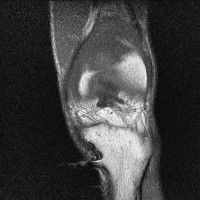

무릎 mri 간단히 봐주실 수 있으시나요 ㅠㅠ

안녕하세요 8년전 십자인대 수술하고 최근 무리한 운동에 무릎 불편감이 생겨서

mri 찍었습니다.

진단결과는 첫 찍은 병원에서 활액막염 이라는 진단을 받았습니다. 혹시 봐주실 수 있으실까요?

진단결과가 달라 혼란스럽습니다 ㅠㅠ

• 안녕하세요. 강성주 의사입니다.

올라온 MRI가 단편적이라서 정확한 진단에 어려움이 있지만 십자인대에는 큰 이상이 있지는 않은것 같으며, 무릎관절내 물이 있는 것으로 보아 활액막염의 진단이 맞을 것 같습니다.

하지만 단편적인 영상이기 때문에 촬영병원에서 정확한 판독지 등을 받으시는 것이 좋겠습니다.